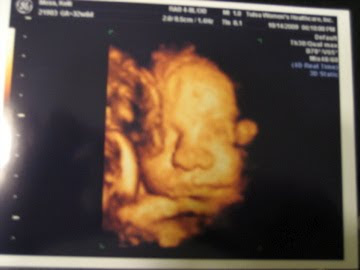

brother FINALLY showed us his face today!!! what a beautiful face. we have a picture of canon that is very similar to this one, and they actually look alike if you can say that while still in utero. he weighs 4 lbs 9 oz. he was measuring about 2 weeks ahead of his due date up until this appointment. now, he's only 5 days ahead of schedule. he's in the 50th percentile which is more than his "big" brother can say. he was wiggly during the ultrasound. i'm telling you, the boy doesn't sit still very often!

what a sweet little face. i cant wait to see him in real life. you look so adorable pregnant. i love that belly. i can't believe that you're already 33 weeks along. yay!

Can't wait to see that sweet face!